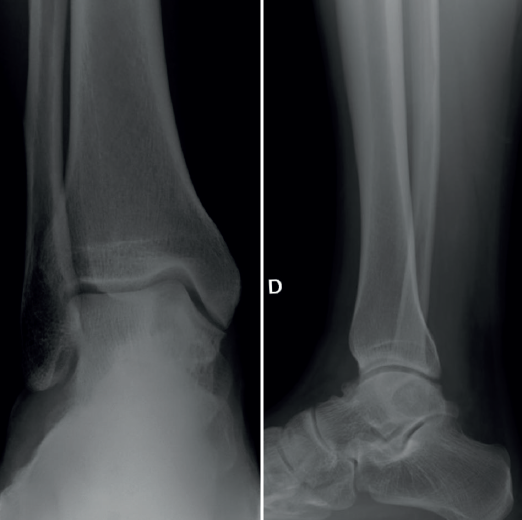

Se presenta el caso de un varón de 33 años con clínica de dolor y limitación funcional en el tobillo derecho de 3 años de evolución. Los estudios por imagen mostraron una lesión de tipo quístico de 2 × 1 ×2,3 cm (diámetros anteroposterior, transversal y craneocaudal), de márgenes geográficos, en el cuerpo del astrágalo, con extensiones filiformes a la articulación tibioastragalina, a nivel de la cúpula medial, que fue orientado en las pruebas radiográficas iniciales como un posible ganglión intraóseo (Figura 1).

Radiográficamente, la lesión se caracteriza por un área radiolúcida circular u ovalada bien definida, bordeada por un borde de hueso esclerótico más denso(9).